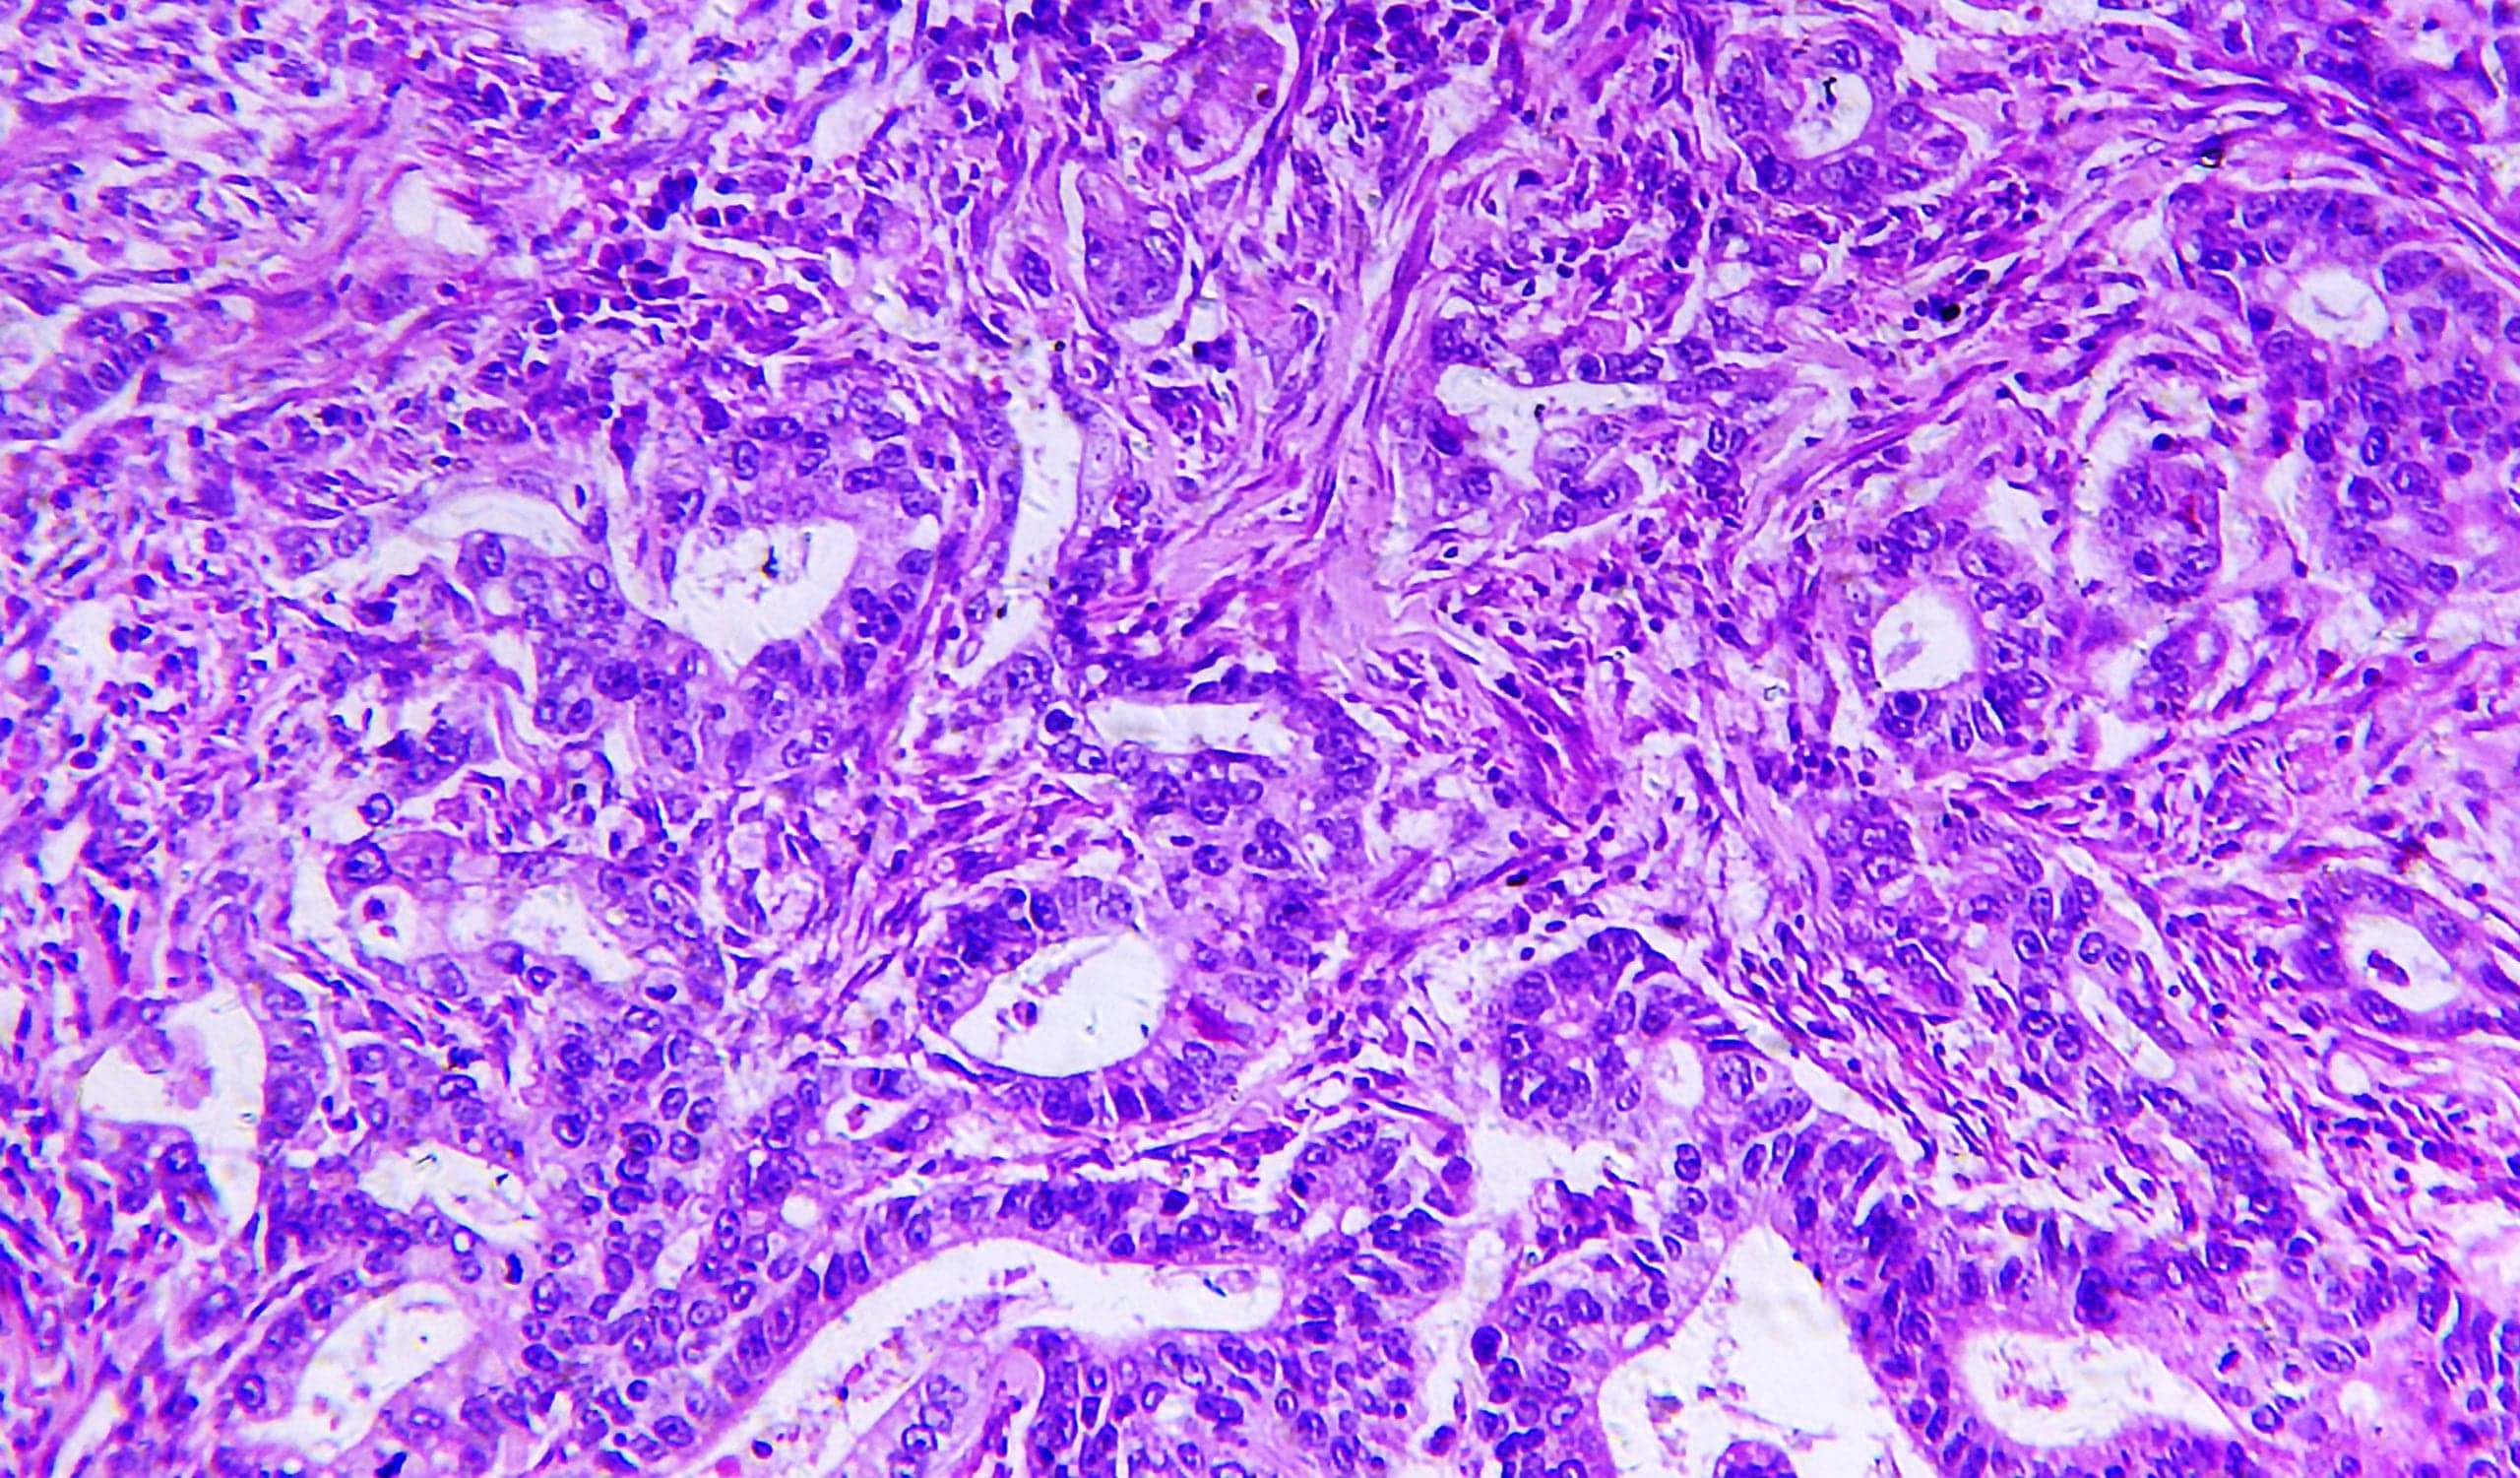

Фотографии опухоли медуллярной аденокарциномы

Раздел: Снимки-откровения